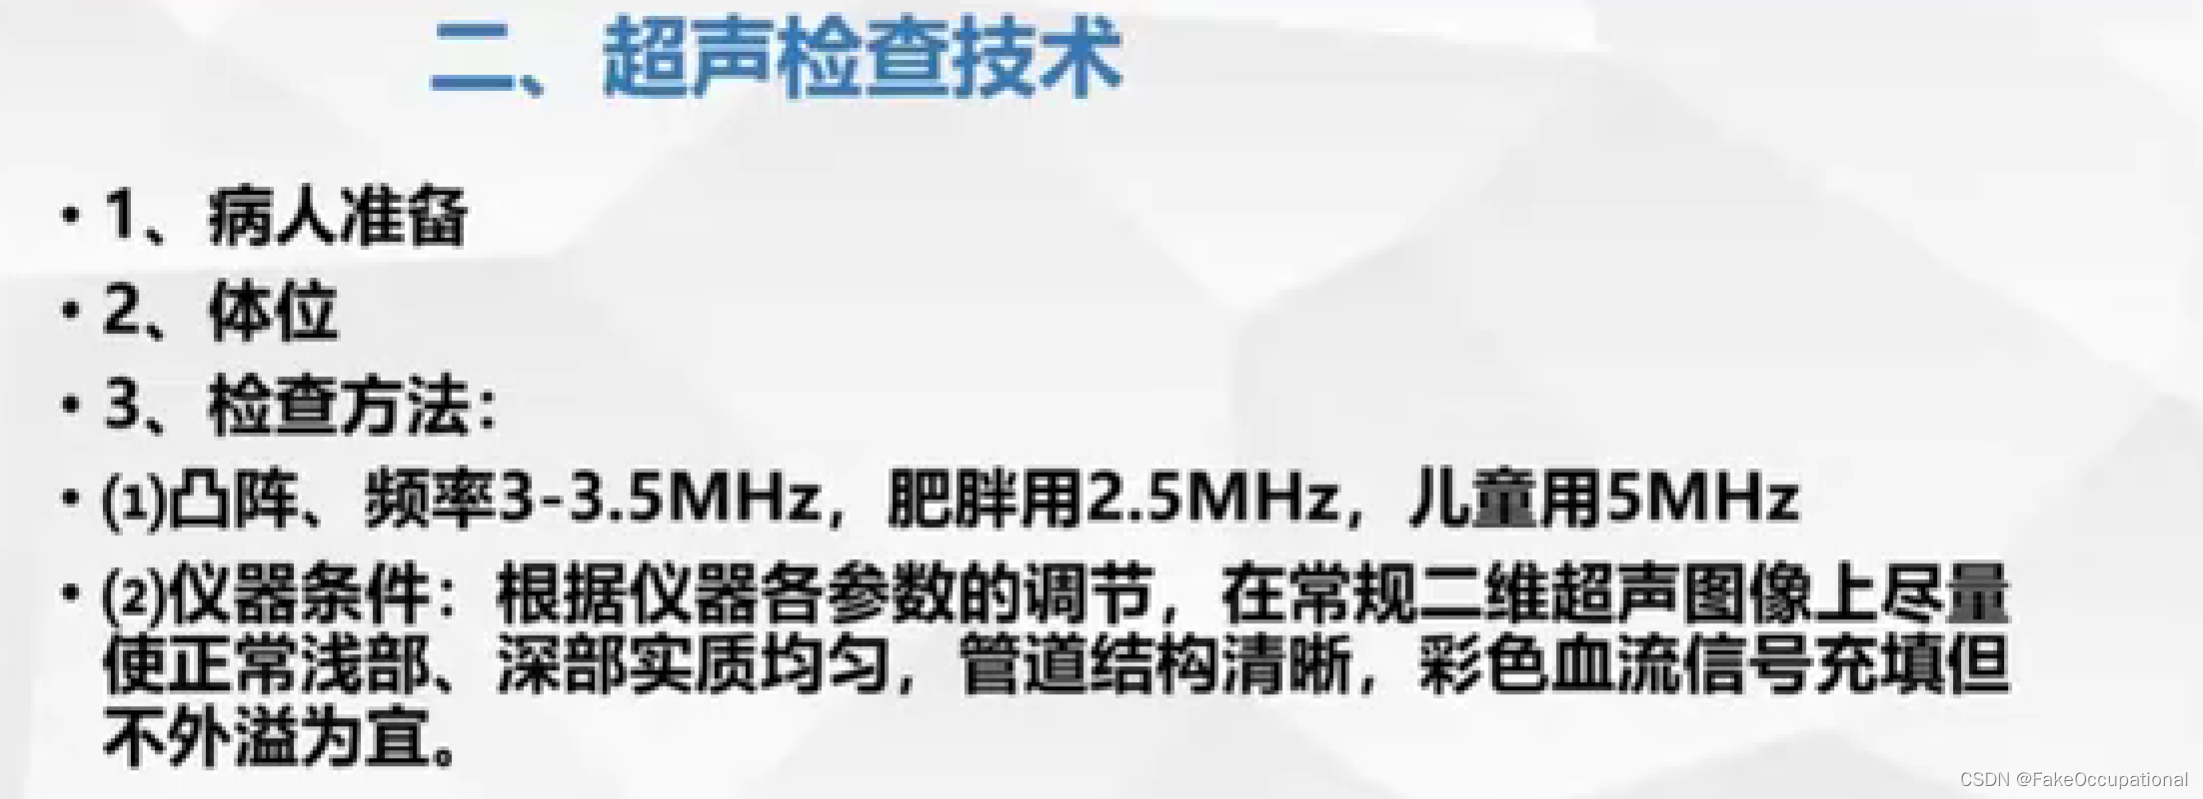

肝脏超声检查技术